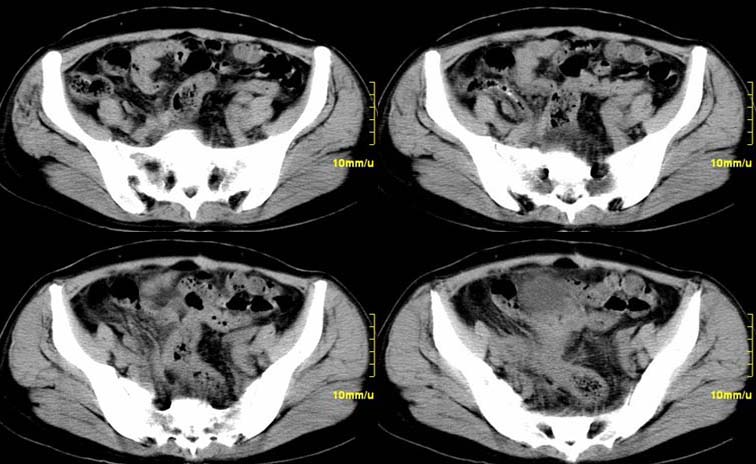

患者,52,右下腹疼痛一月,当时有发热,抗炎治疗20余天,至今仍疼痛,且有低热。

增强

右附件区软组织包块,内囊变坏死,边缘模糊,与子宫,与膀胱分界不清,增强强化与子宫密度相近.盆腔内无肿大淋巴结考虑炎性包块可能性大。

右附件区软组织包块,内可见坏死,边界不清,周围软组织及脂肪组织可见密度增高,膀胱右侧壁增厚,并且呈膨胀不全的改变,考虑炎性包裹,不知道有没有手术史??

临床特点:

右下腹疼痛一月,当时有发热,抗炎治疗20余天,至今仍疼痛,且有低热,具有典型炎症的临床表现。

ct表现:

右侧附件见一肿块,边缘与周围组织分界不清,增强扫描见肿块明显强化,越到后期强化越明显,中央见坏死,内壁光整,与临近子宫壁、直肠及膀胱后壁均见炎症波及。这种厚壁肿块、内缘光整外缘模糊、增强扫描强化越后越强是附件脓肿典型的ct表现。

诊断:

右侧卵巢输卵管慢性脓肿,炎症波及临近子宫、直肠及膀胱形成粘连。